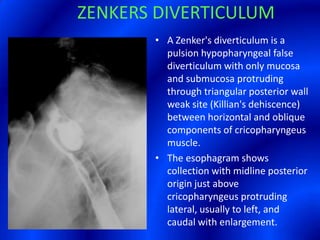

This document provides information about a barium swallow procedure. It begins with an introduction and overview of the embryology and anatomy of the pharynx and esophagus. It then describes the procedure itself, including preparation, technique, views obtained, and indications. Specific conditions that may be examined include pharyngeal and esophageal webs, foreign body impaction, scleroderma, dysphagia, mediastinal masses, and carcinoma. Diagrams are provided to illustrate normal anatomy and various pathological findings.